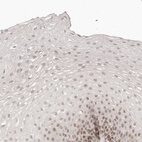

Immunohistochemical staining of human esophagus shows moderate nuclear positivity in squamous epithelial cells.